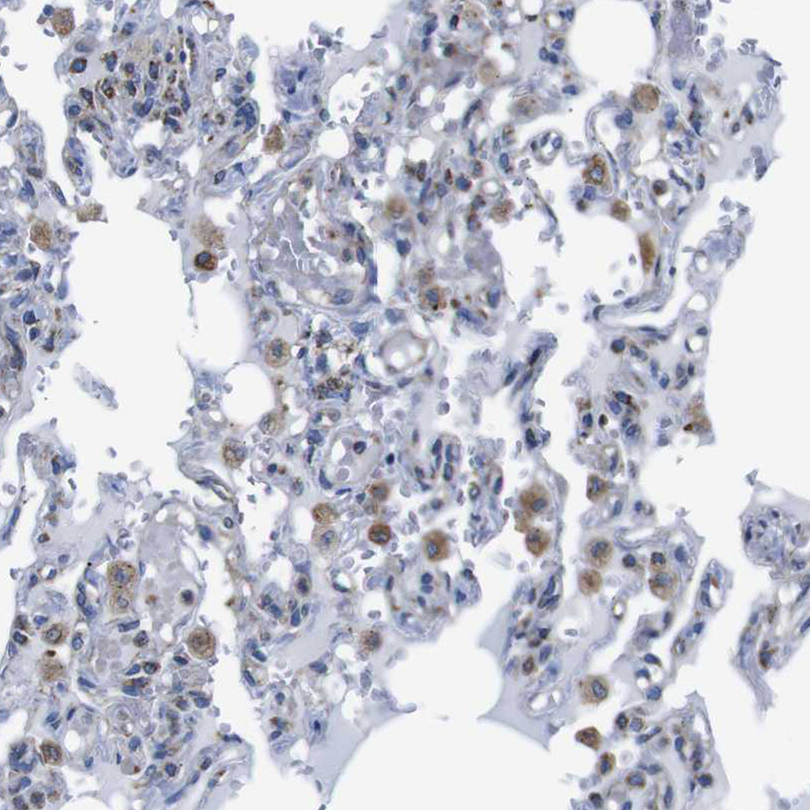

Immunohistochemical staining of human lung shows moderate cytoplasmic positivity.